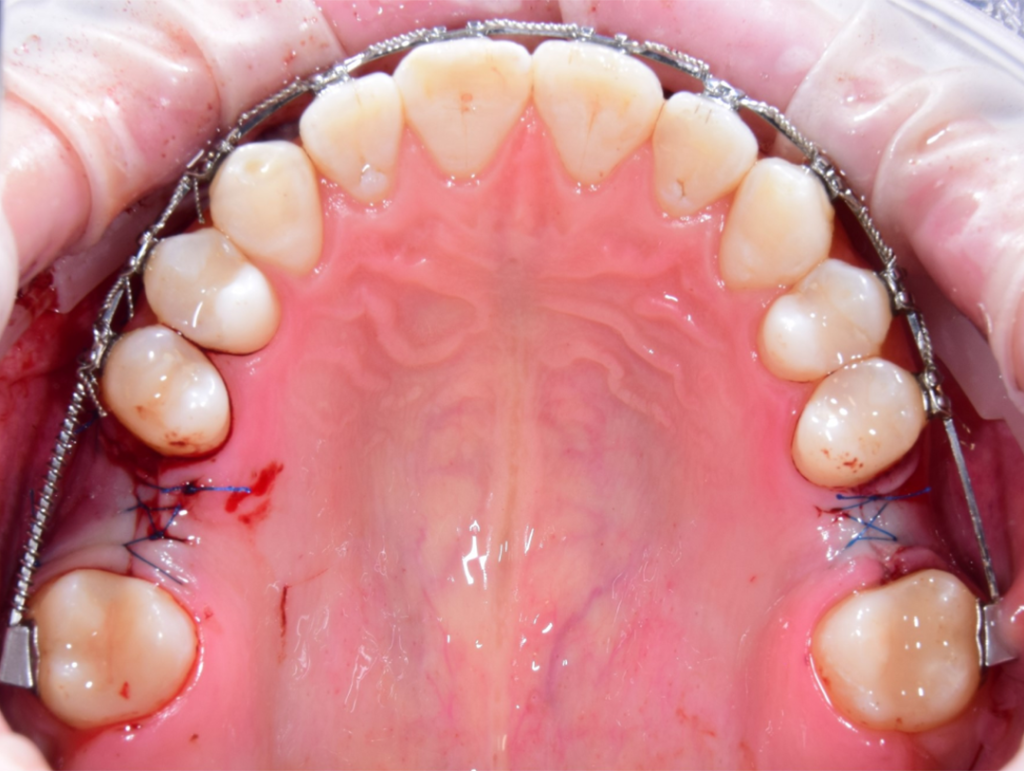

По результатам диагностики принято решение провести синус-лифтинг с помощью боров SinPro. В ходе вмешательства установлены имплантаты AnyRidge и AnyOne с первичной стабилизацией 40 Ncm.